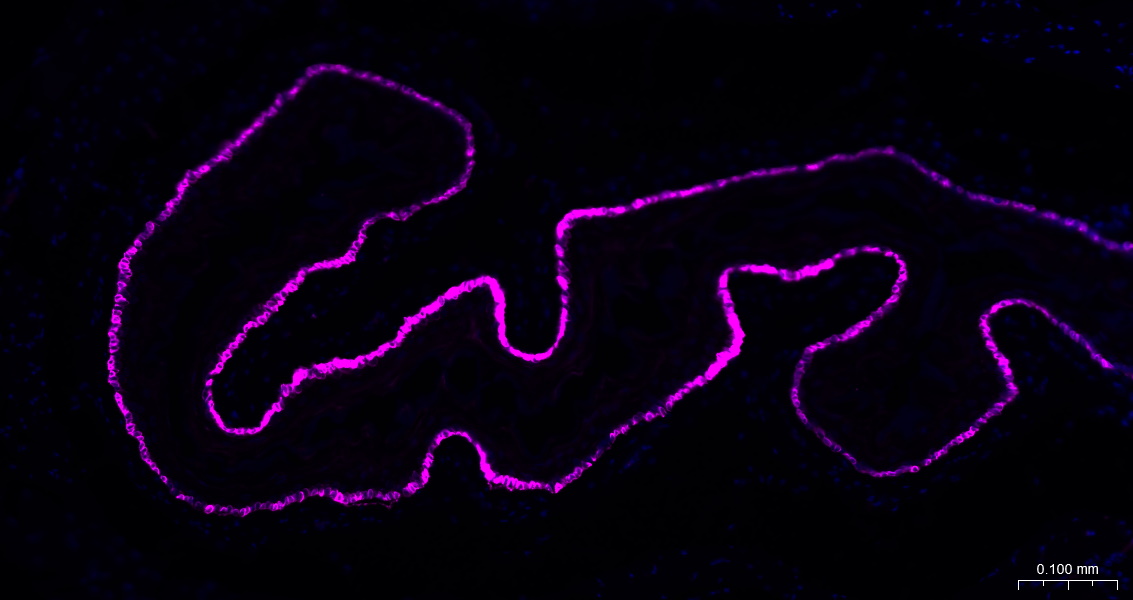

Paraformaldehyde-fixed, paraffin embedded Rat Esophagus; Antigen retrieval by boiling in sodium citrate buffer (pH6.0) for 15 min; The section was incubated with Cytokeratin 14 Monoclonal Antibody, Unconjugated (bsm-52054R) at 1:500 overnight at 4°C. Followed by conjugated Goat Anti-Rabbit IgG antibody (Rose Red, bs-0295G-BF647), DAPI (blue, C02-04002) was used to stain the cell nuclei.

Paraformaldehyde-fixed, paraffin embedded Mouse Esophagus; Antigen retrieval by boiling in sodium citrate buffer (pH6.0) for 15 min; The section was incubated with Cytokeratin 14 Monoclonal Antibody, Unconjugated (bsm-52054R) at 1:500 overnight at 4°C. Followed by conjugated Goat Anti-Rabbit IgG antibody (Rose Red, bs-0295G-BF647), DAPI (blue, C02-04002) was used to stain the cell nuclei.